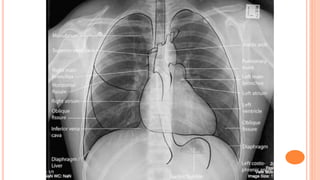

Normal Chest X-Ray

PA LAT

Airways

Bones

Cardiac